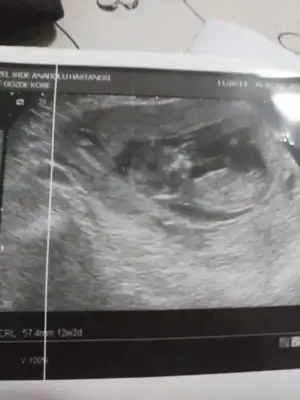

Banada bakarmısınız 12+2 günlükErkek ve kız için 11 yada 12 hafta usg görüntüsü olmalı açıklamalar asagıda yazıyorrabbim herkesin gönlüne göre nasip etsin inşallah .. ecmain

yine kız yönünde nubuMerhaba. 11. Hafta Usg paylasmistim, kiz olabilir yeniden paylasin demistiniz. Su an 13. Hafta goruntusunu ekliyorum. Tahmin alabilir miyim? Tesekkur ederim. Eki Görüntüle 2593830

yine kız yönünde nubu![]()